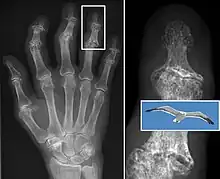

Diagnosis is made with reasonable certainty based on history and clinical examination.[42][43] X-rays may confirm the diagnosis. The typical changes seen on X-ray include: joint space narrowing, subchondral sclerosis (increased bone formation around the joint), subchondral cyst formation, and osteophytes.[44] Plain films may not correlate with the findings on physical examination or with the degree of pain.[45] Usually other imaging techniques are not necessary to clinically diagnose osteoarthritis.

Severe osteoarthritis and osteopenia of the carpal joint and 1st carpometacarpal joint.

Both primary generalized nodal osteoarthritis and erosive osteoarthritis (EOA, also called inflammatory osteoarthritis) are sub-sets of primary osteoarthritis. EOA is a much less common, and more aggressive inflammatory form of osteoarthritis which often affects the distal interphalangeal joints of the hand and has characteristic articular erosive changes on x-ray.[52]